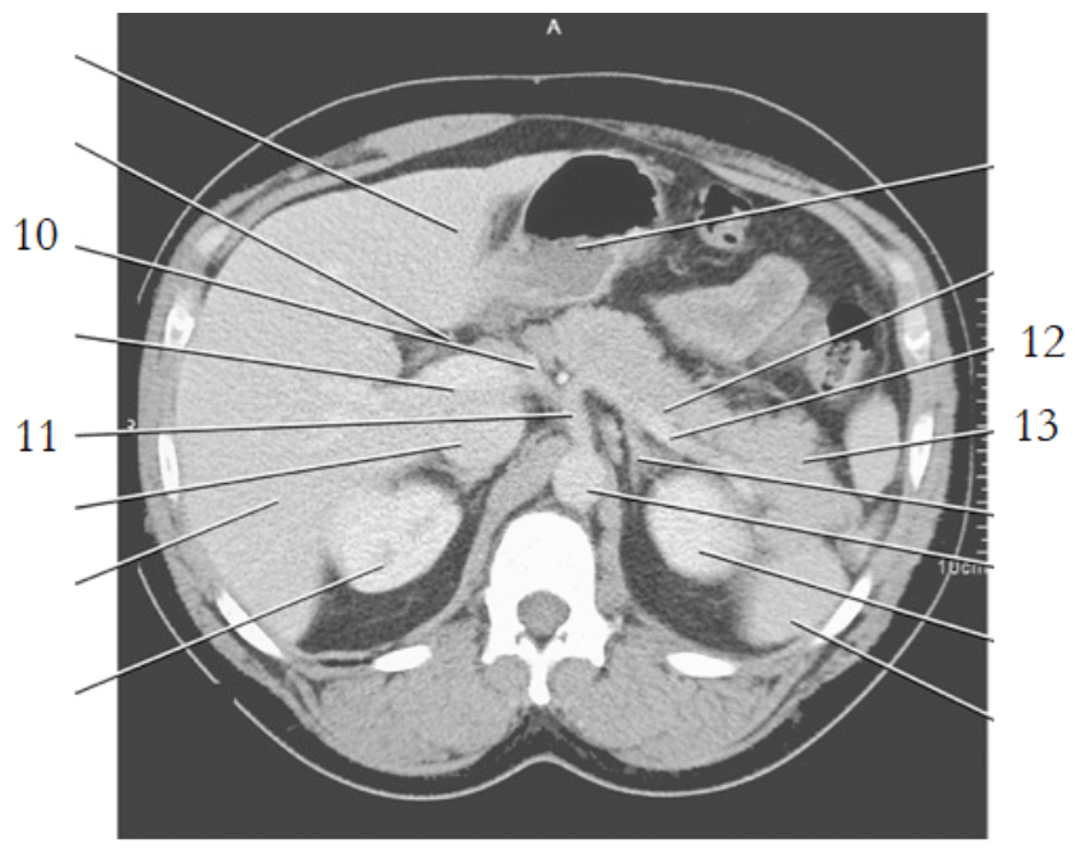

11

celiac axis

12

splenic artery

15

portal vein

20

aorta

24

19

left renal vein

1

liver

3

esophagus

stomach

spleen

9

crus of diaphragm

8

IVC

13

pancreas tail

16

kidney

14

gallbladder

4

left renal artery

small bowel

21

large bowel

25